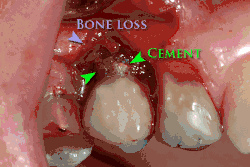

Cement peri-implantitis

Dental cement under the gingiva causes peri-implantitis and implant failure.

Beyond the possibility of mechanical failure[98] which may be due to poor prosthetic fitment, wear and tear, or user-induced actions such as bruxism, dental implants are also subject to peri-implant mucositis and peri-implantitis, where gum tissue and bone mass around the implant are resorbed, and the implant gradually becomes loose, and has to be removed.[99][100] In addition, although titanium is generally well tolerated by the body, there have been cases where the build-up of titanium particles released by the implant may cause systemic inflammatory response.[101] Because there is no dental enamel on an implant, it does not fail due to cavities like natural teeth. While large-scale, long-term studies are scarce, several systematic reviews estimate the long-term (five to ten years) survival of dental implants at 93–98 percent depending on their clinical use.[15][16][17] During initial development of implant retained teeth, all crowns were attached to the teeth with screws, but more recent advancements have allowed placement of crowns on the abutments with dental cement (akin to placing a crown on a tooth). This has created the potential for cement, that escapes from under the crown during cementation to get caught in the gingiva and create a peri-implantitis (see picture below). While the complication can occur, there does not appear to be any additional peri-implantitis in cement-retained crowns compared to screw-retained crowns overall.[102] In compound implants (two stage implants), between the actual implant and the superstructure (abutment) are gaps and cavities into which bacteria can penetrate from the oral cavity. Later these bacteria will return into the adjacent tissue and can cause periimplantitis.